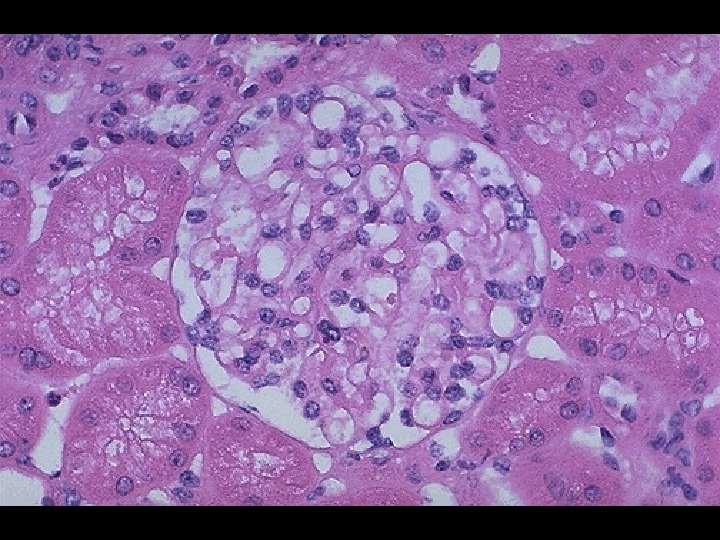

POST-STREPTOCOCCAL ACUTE GLOMERULONEPHRITIS (PSAGN) * Non-suppurative sequelae following pharyngitis and skin infections by Group A Streptococcus (GAS) * 1 to 3 weeks following pharyngitis and skin infections * Characterized by • Edema (peri-orbital) • Hematuria • Hypertension * Male to female ratio of 2: 1

POST-STREPTOCOCCAL ACUTE GLOMERULONEPHRITIS (PSAGN) * Highest incidence/prevalence between 4 to 12 years * Antigens from "Nephritogenic strains“ * M 2, M 12, M 49, M 57, M 59, M 60 * Effector mechanism • Deposition of soluble immune complexes in glomeruli * Laboratory diagnosis • Anti-streptolysin O (ASO) [skin infections show poor response] • Anti-DNase. B • C 3

SYSTEMIC LUPUS ERYTHEMATOSUS (SLE) * Effector mechanisms • Autoantibodies to many autoantigens • Most common autoantibody is to ds-DNA • Immune complex deposition on basement membranes with complement activation and inflammation * Laboratory diagnosis • Anti-nuclear antibody (ANA) • IFA (indirect fluorescent antibody) assay using HEp-2 cells • Homogeneous pattern and titer > 1: 160 • Anti ds-DNA • IFA assay using Crithidia lucilliae • C 3 level